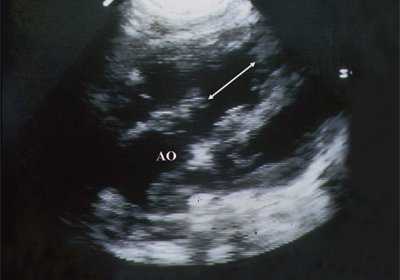

В равной степени это относится к дефекту межжелудочковой перегородки (рис. 6), простой форме транспозиции магистральных сосудов (рис. 7, 8), транспозиции магистральных сосудов с дефектом межжелудочковой перегородки (синдром Тауссиг - Бинга) (рис. 9), общему желудочку (рис. 10), общему артериальному стволу (рис. 10), двойному отхождению сосудов от одного из желудочков сердца (рис. 11).

Рис. 6. Дефект межжелудочковой перегородки. Длинная ось сердца. Стрелками показан дефект межжелудочковой перегородки.

Рис. 11. Двойное отхождение магистральных сосудов от левого желудочка. Длинная ось сердца. Магистральные сосуды инвертированы и отходят от левого желудочка. Аорта расположена "верхом" над дефектом межжелудочковой перегородки (стрелка).

LV и RV - левый и правый желудочек, АР - легочная артерия, АО - аорта, VSD - дефект межжелудочковой перегородки.